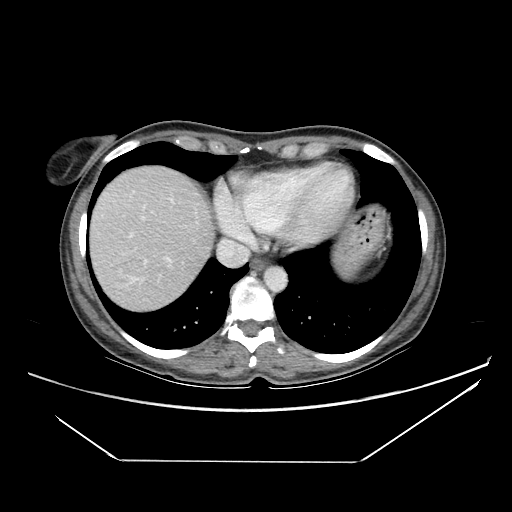

Original VENOUS CT scan

Full window (WL 1023.5, WW 4095 β†’ Low βˆ’1024, High +3071)

Actual HU range: [-160.0, 240.0]